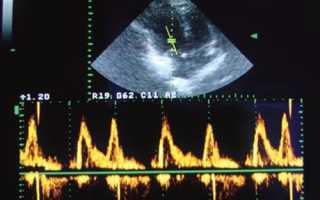

Далеко не всегда, человеку, у которого выявили снижение диастолической функции левого желудочка, в конечном счете, ставят диагноз сердечная недостаточность хронического типа, поскольку для этого необходимо также наличие других характерных признаков, а также небольшое снижение показателей фракции выброса. Решение о постановке диагноза принимается доктором после тщательного исследования работоспособности всех частей миокарда, а также на основе результатов диагностических процедур.